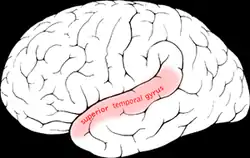

Superior temporal gyrus of the human brain. | |

Position of superior temporal gyrus (shown in red).